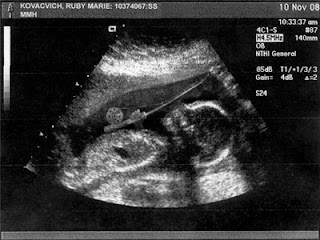

I would much rather see thisL